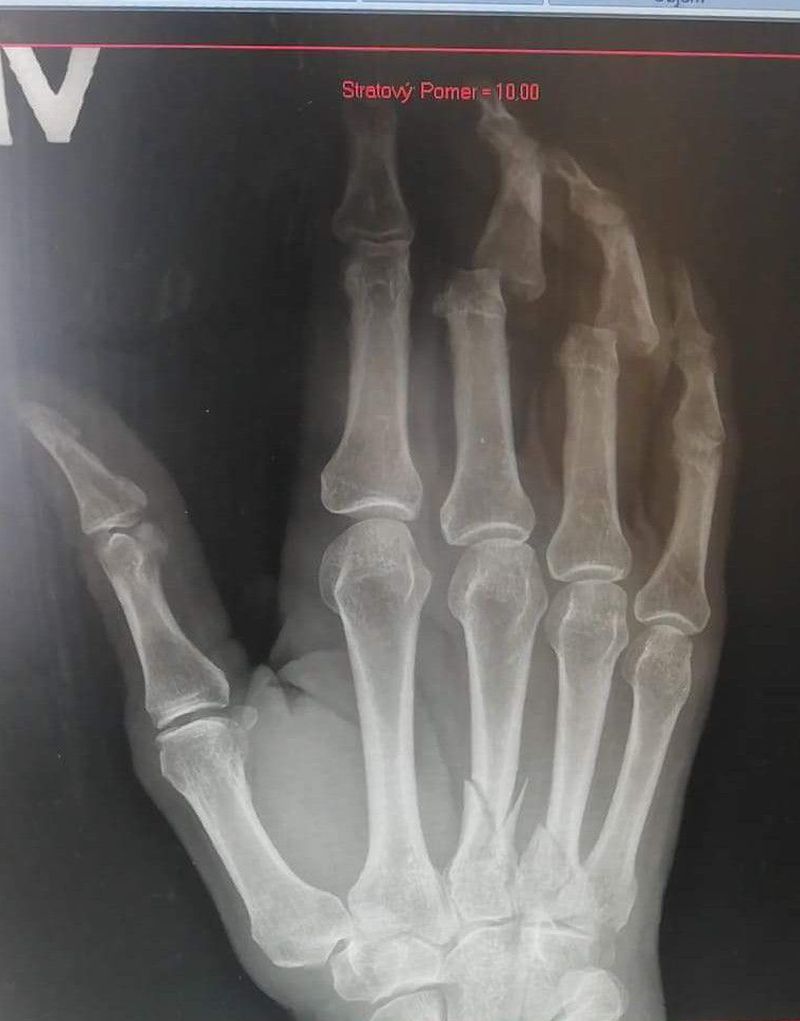

Little work injury... Fall from train

Nice. In Your hospital - would you treat those metacarpal fractures operatively or non-operatively? In my hospital we would give to patient cast and make control x-ray after 7-10 days.

No special treat, just splint for two weeks and control rtg

# 3rd and 4th fingers